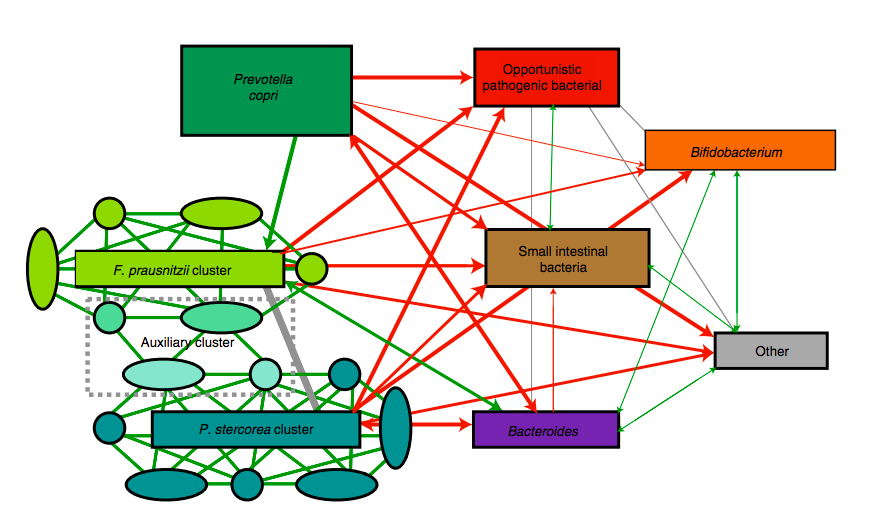

I batteri che abitano l’intestino umano sono strutturati come un ecosistema complesso che viene continuamente

Il microbiota intestinale è un ecosistema mutevole e continuamente modellato da fattori come ambiente, stile

Il microbiota dell’intestino è un ambiente diversificato che ospita la maggior parte dei nostri microbi

È ormai validato scientificamente che il microbiota intestinale svolge un ruolo fondamentale nella formazione e

Un numero crescente di studi evidenzia che la disbiosi intestinale è associata allo sviluppo della